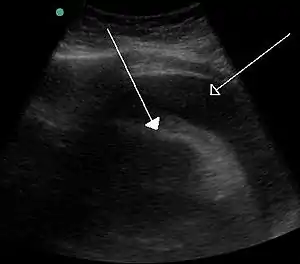

Однак найзагрозливіші наслідки при виниканні тампонади внаслідок проблем зі здоров'ям, як у випадку тампонади серця. У цій ситуації рідина збирається всередині перикардіального мішка. Тиск у перикарді не дає серцю повністю розширитися і заповнити шлуночки, унаслідок чого в організмі циркулює значно зменшена кількість крові. Якщо не зупинити цей стан, при таких обставинах можлива смерть.